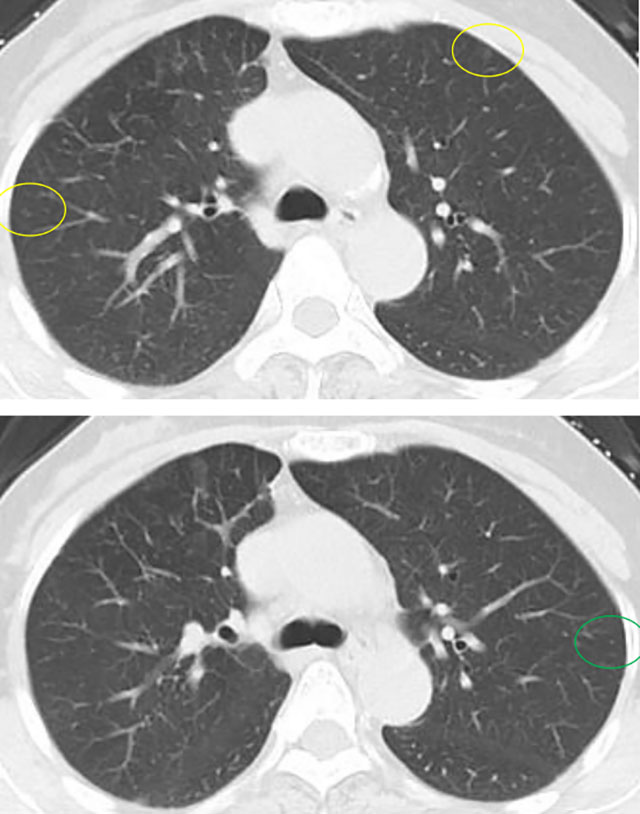

几年前,一位阿姨体检发现双肺多发10余个磨玻璃结节,最大位于右肺上叶,约9mm。当时判断:多为低风险,医生建议半年随访。

几年前影像展示与分析,5mm层厚、无薄层。

上图中红色圈原位癌可能性较大,尤其右肺上叶尖段二个结节,可见血管增粗及血管弯5mm层厚,无薄层重建;橙色圈多考虑不典型增生可能性大;黄色圈大概只是肺泡上皮增生;绿色圈考虑是良性的。